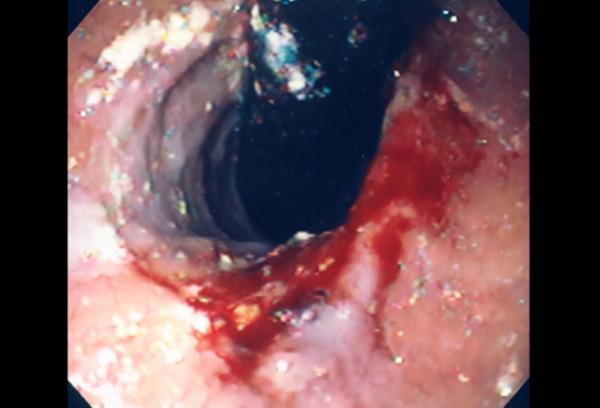

食管損傷

50歲男性,長期酗酒史,近期食管造影診斷出已知食管靜脈曲張(紅色箭頭),因嘔血而到急診室就診。他的朋友報告說道,這名男子當天早些時候酗酒,大約1小時前開始嘔吐。患者的初始生命體徵顯示心率為90次/分,血壓為 115/73 mmHg,呼吸頻率正常。當他坐在候診室裡時,他已經用兩個杯子裡裝滿了含有血液的紅色液體。

在開始靜脈液體給藥後,如何進行下一步管理,包括警惕等待、重複食管造影、胸部、腹部和骨盆CT、胃腸道內窺鏡檢查、血管造影的介入放射學諮詢。

答案是胃腸道內窺鏡檢查。患者就診的病史提示食管靜脈曲張出血或馬洛裡-魏斯綜合徵,這兩種病史都可以透過內鏡檢查進行診斷和管理。靜脈曲張繼發於肝硬化,肝硬化會改變脈管系統的壓力和流量梯度。隨著靜脈曲張大小的增加,破裂和出血的風險急劇增加,再出血的機率為70%。其他臨床症狀包括嘔吐物中的血液、頭暈目眩、心率加快、意識喪失及黑色、柏油或血腥的糞便。